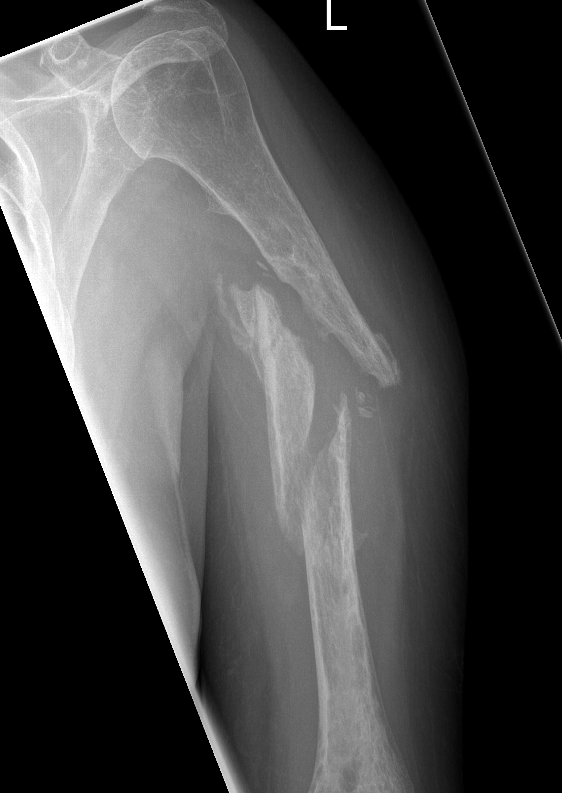

Union of a midshaft humerus fracture treated nonoperatively

Union of distal humerus fracture treated nonoperatively